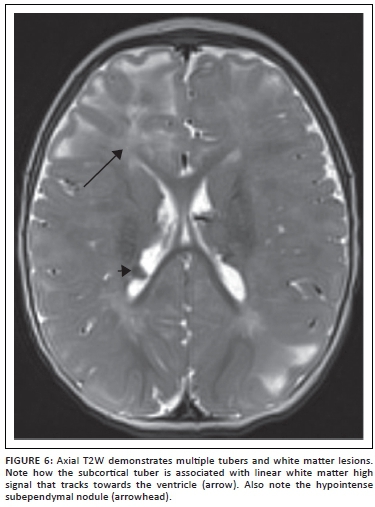

Perinatal stroke

There is a significant risk of developing epilepsy after perinatal stroke, hypoxic-ischaemic injury, and intracerebral haemorrhage (Figure 9). Seizures can become refractory to medications in approximately 25% of these patients.22 Challenges in managing seizures in these patients include multifocal or bilateral cortical injury, non-focal or poorly lateralising video electroencephalography (EEG) findings, and limited functional reserve. Seizure onset zone may not be limited to the abnormality identified on imaging studies, and subdural electrode placement for invasive monitoring may be required. In addition to acquiring a functional MRI, we track the corticospinal, visual and language pathways using diffusion tensor imaging and tractography to aid the neurosurgeon in developing a resection plan. When surgical resection is planned using this approach, functional outcomes are generally good in this group of patients, with improvements in independence, quality of life, cognitive development and motor skills, despite transient postoperative monoparesis or hemiparesis and occasional mood disorders.